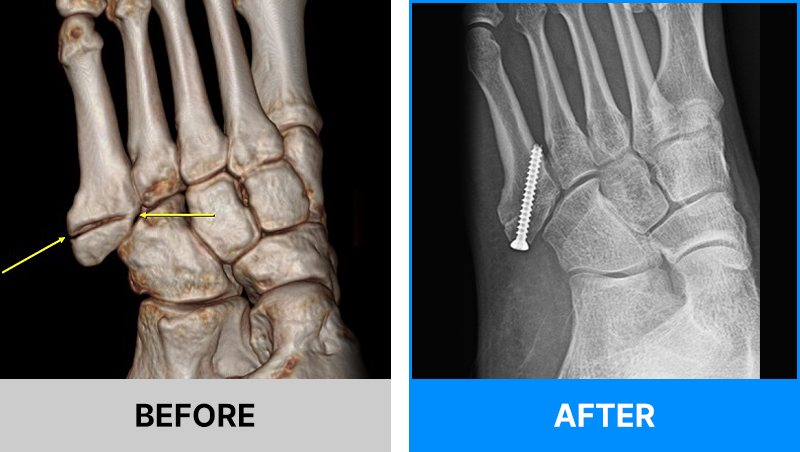

왜 당일 입퇴원 수술일까요?

오래 입원할 필요가 없기 때문입니다.

서울거탑정형외과에서는 전신마취, 척추마취가 아닌

국소부분마취(신경차단) 및 수면 마취를 통해 수술을 시행합니다.

수술 가능 여부 확인은 대표원장과의 진료가 필요합니다.